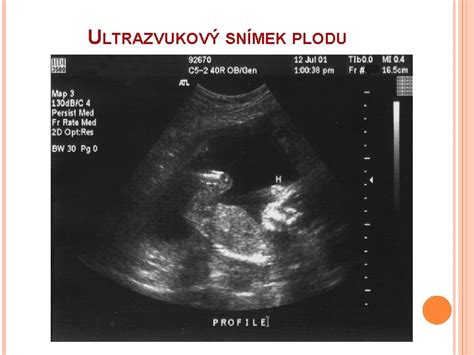

Léčba nízko položené placenty neexistuje. Klíčové je pravidelné sledování její polohy ultrazvukem. V některých případech může lékař doporučit klid na lůžku, omezení fyzické námahy a vyhýbání se sexuální aktivitě.